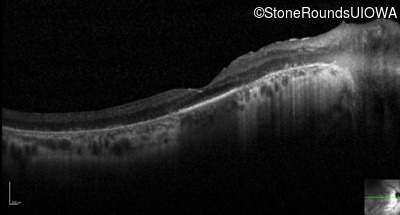

Optical Coherence Tomography - Left - 20/70

Exemplar / OCT Stack